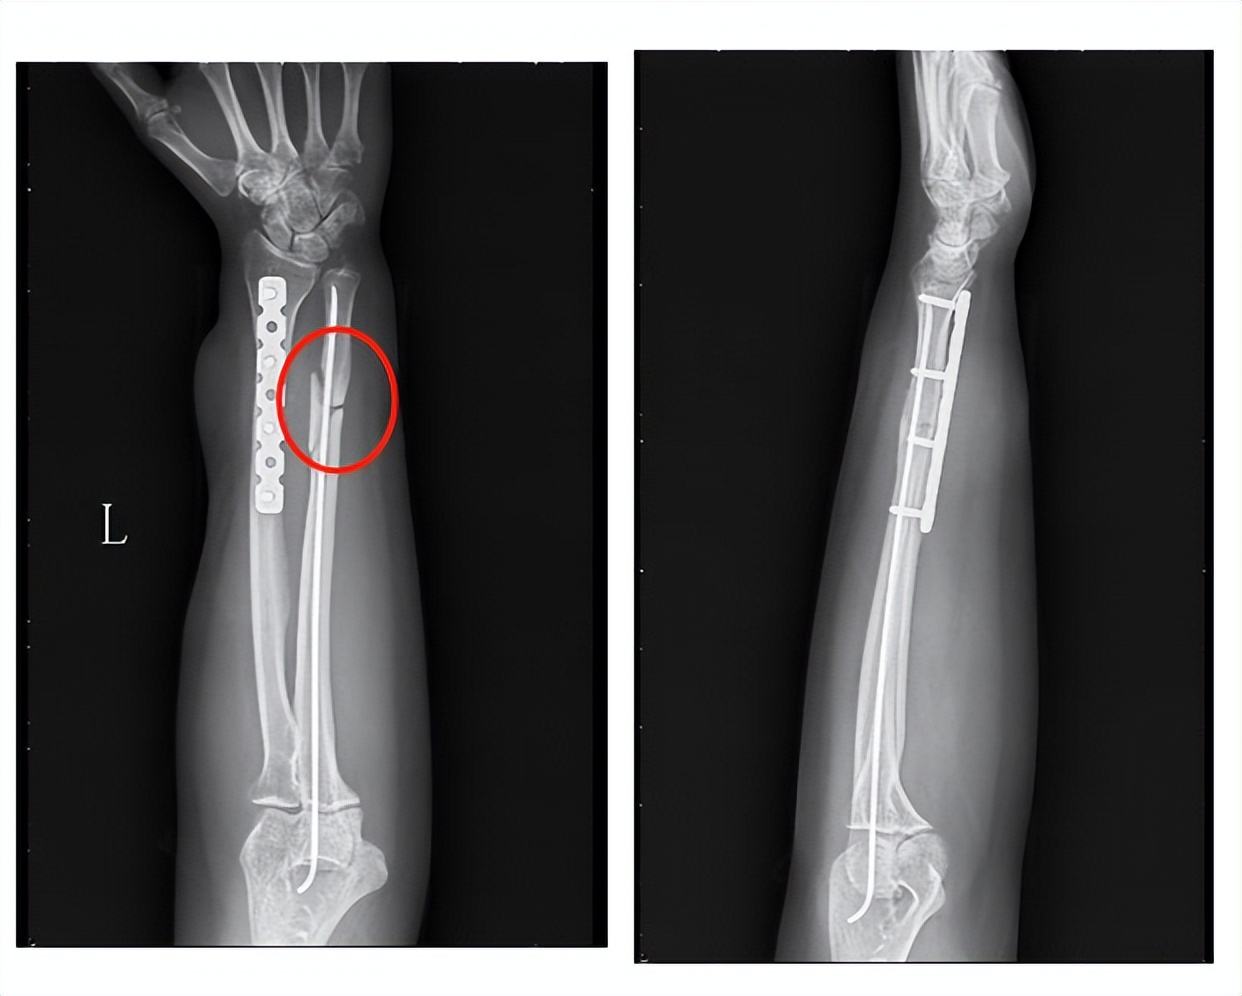

由于病人初次选择的是闭合复位的方式,创伤外科团队在仔细分析后,认为这个骨块仍然是有生物活性的。在和患者充分沟通后,在隋院长的主持下,创伤外科团队采用了生长因子注射的微创治疗方式。

(手术中定位,注射生长因子)

在C臂机的引导下定位骨不连区域,隋院长为患者注射生长因子,整个治疗过程不到5分钟时间,治疗结束后局部只有一个针眼。

大家一定很关心,这么微创的治疗方式,能不能治愈这个骨不连。这是病人手术治疗后3个月回来复查的X线片,大家可以看到骨不连的区域已经完全实现了骨性的愈合,间隙已经消失了。

(生长因子注射术后3个月)

在术后6个月的时候,在病人的要求下,取出了钢板和弹性钉。病人最后一次来医院的时候,前臂的腕关节的背伸功能、掌曲功能以及前臂的旋转功能已经完全接近正常。骨不连完全愈合,这个愈合速度其实已经超出了传统植骨手术,而且没有给病人增加额外的创伤,病人对这种治疗方式非常满意。

(生长因子注射术后6个月去除内置物)